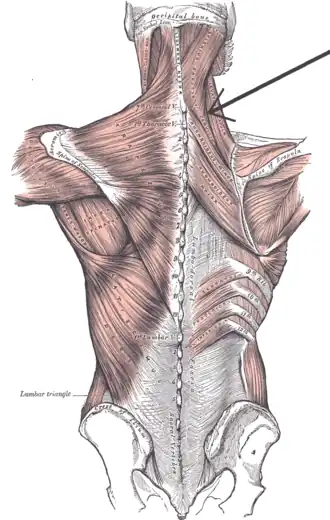

Muscles connecting the upper extremity to the vertebral column. (Splenius capitis et cervicis labeled at upper right, at neck.) | |

The splenius cervicis (/ˈspliːniəs sərˈvaɪsɪs/) (also known as the splenius colli, /- ˈkɒlaɪ/) is a muscle in the back of the neck. It arises by a narrow tendinous band from the spinous processes of the third to the sixth thoracic vertebrae; it is inserted, by tendinous fasciculi, into the posterior tubercles of the transverse processes of the upper two or three cervical vertebrae.